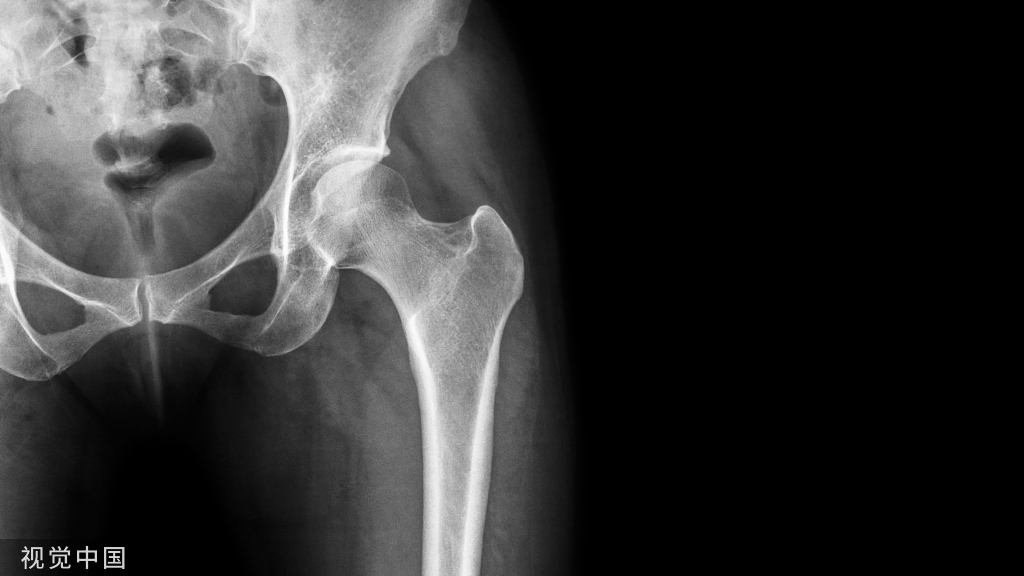

虽然有所防备,但有时难免发生意外。这时,患者可以先自行评估是否出现关节畸形移位或形成假关节(骨头断裂)等,如果遇到这类严重情况应固定后立即就医,如果只是局部的肿胀瘀斑,疼痛程度较低,就可以先自我急救。伤者在进行急救处理后,如有条件最好在医院进行X线或CT检查,因为小骨头的断裂或撕裂等问题并不会引起强烈的疼痛或肿胀等,但如果没有有效的医疗支具固定可能会致骨折错位或损伤进一步加剧,后期恢复不充分,还会导致陈旧性软组织受伤,在关节尤其负重部位容易引发骨关节病等慢性疾病。

X线片:基本的辅助检查(应注意某些情况并非骨折)CT:能进一步检查隐匿性骨折或撕脱性骨折MRI:可检查肌腱、韧带的损伤肌骨超声:可代替或结合MRI检查软组织的损伤

X线